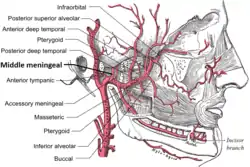

Plan of branches of the maxillary artery. | |

The middle meningeal artery (Latin: arteria meningea media) is typically the third branch of the first portion of the maxillary artery. After branching off the maxillary artery in the infratemporal fossa, it runs through the foramen spinosum to supply the dura mater (the outer meningeal layer) and the calvaria. The middle meningeal artery is the largest of the three (paired) arteries that supply the meninges, the others being the anterior meningeal artery and the posterior meningeal artery.

It ascends between the sphenomandibular ligament and the lateral pterygoid muscle, and between the two roots of the auriculotemporal nerve to the foramen spinosum of the sphenoid bone, through which it enters the cranium; it then runs forward in a groove on the great wing of the sphenoid bone, and divides into two branches, anterior and posterior.

The anterior branch, the larger, crosses the great wing of the sphenoid, reaches the groove, or canal, in the sphenoidal angle of the parietal bone, and then divides into branches that spread out between the dura mater and internal surface of the cranium, some passing upward as far as the vertex, and others backward to the occipital region.

The posterior branch curves backward on the squamous part of the temporal bone, and, reaching the parietal bone some distance in front of its mastoid angle, divides into branches that supply the posterior part of the dura mater and cranium.

The branches of the middle meningeal artery are distributed partly to the dura mater, but chiefly to the bones; they anastomose with the arteries of the opposite side, and with the anterior and posterior meningeal arteries. The very smallest distal branches anastomose through the skull with small arterioles from the scalp.

On entering the cranium, the middle meningeal artery gives off the following branches:

- Numerous small vessels supply the trigeminal ganglion and the dura mater

- A superficial petrosal branch enters the hiatus of the facial canal, supplies the facial nerve, and anastomoses with the stylomastoid branch of the posterior auricular artery.

- A superior tympanic artery runs in the canal of the tensor tympani muscle, and supplies this muscle and the lining of the canal.

- Orbital branches pass through the superior orbital fissure or through separate canals in the great wing of the sphenoid, to anastomose with the lacrimal or other branches of the ophthalmic artery.

- Temporal branches pass through foramina in the great wing of the sphenoid, and anastomose in the temporal fossa with the deep temporal arteries.